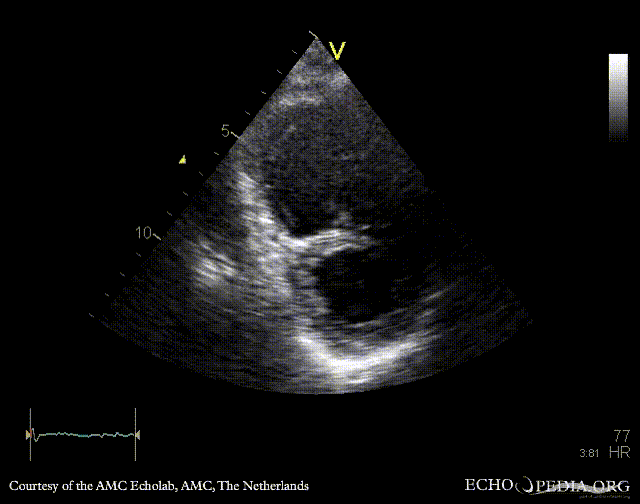

A4CH: stiff, immobile tricuspid valve A4CH: severe tricuspid regurgitation